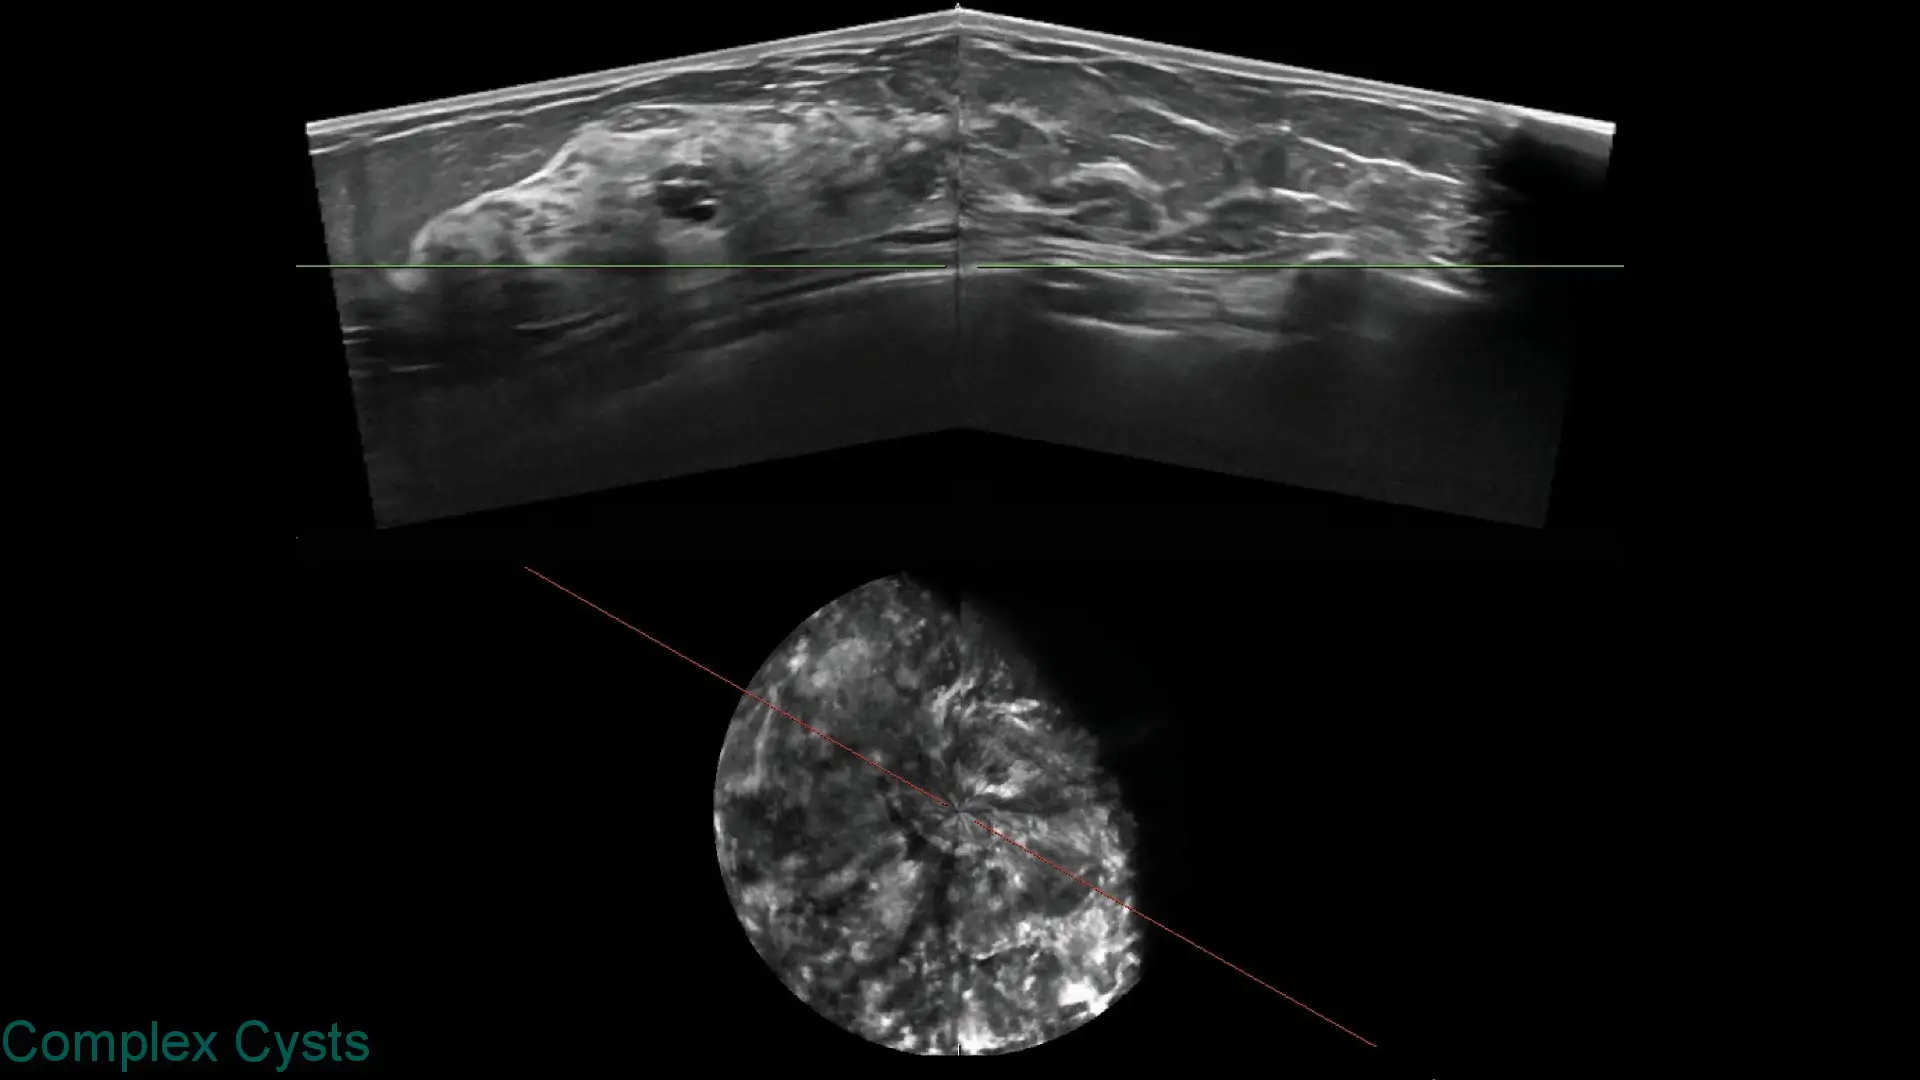

Explore clinical breast ultrasound images captured with SOFIA, showcasing various tissue types and conditions with exceptional clarity.